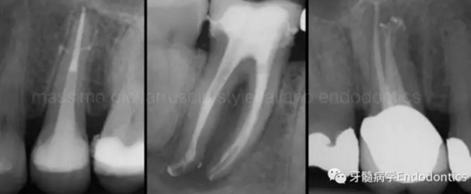

圖1.探查冠方2/3可以獲得有關(guān)根管系統(tǒng)解剖形態(tài)的相關(guān)信息,獲得根管彎曲和多重彎曲程度,或者是否存在根管彎曲的一些重要反饋。醫(yī)生需要重視五種可能遇到的根管解剖類型(包括融合、彎曲、多重彎曲、分歧、分支)。

當(dāng)建立直線通路、找到所有的根管口后,重心應(yīng)轉(zhuǎn)移到根管預(yù)備上。若牙髓存在活力且持續(xù)滲血,應(yīng)使髓室內(nèi)充滿粘性螯合劑。在牙髓已壞死的情況下,應(yīng)使用加熱的5.25%次氯酸鈉溶液沖洗并徹底充滿髓室。探查前,根據(jù)術(shù)前X線片測(cè)量并預(yù)彎小的不銹鋼銼,以順應(yīng)預(yù)估的根管長(zhǎng)度及彎曲度。使用0.02錐度的10號(hào)不銹鋼手用K銼探查根管冠方2/3。